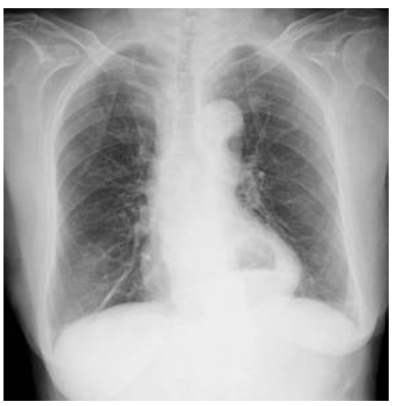

74. 病人主訴胸骨後和上腹部疼痛且食慾不佳,胸部X光檢查呈現如圖,下列那一項診斷最正 確?

(A)hiatal hernia (B)aortic dissection (C)myocardial infarction (D)pneumomediastinum